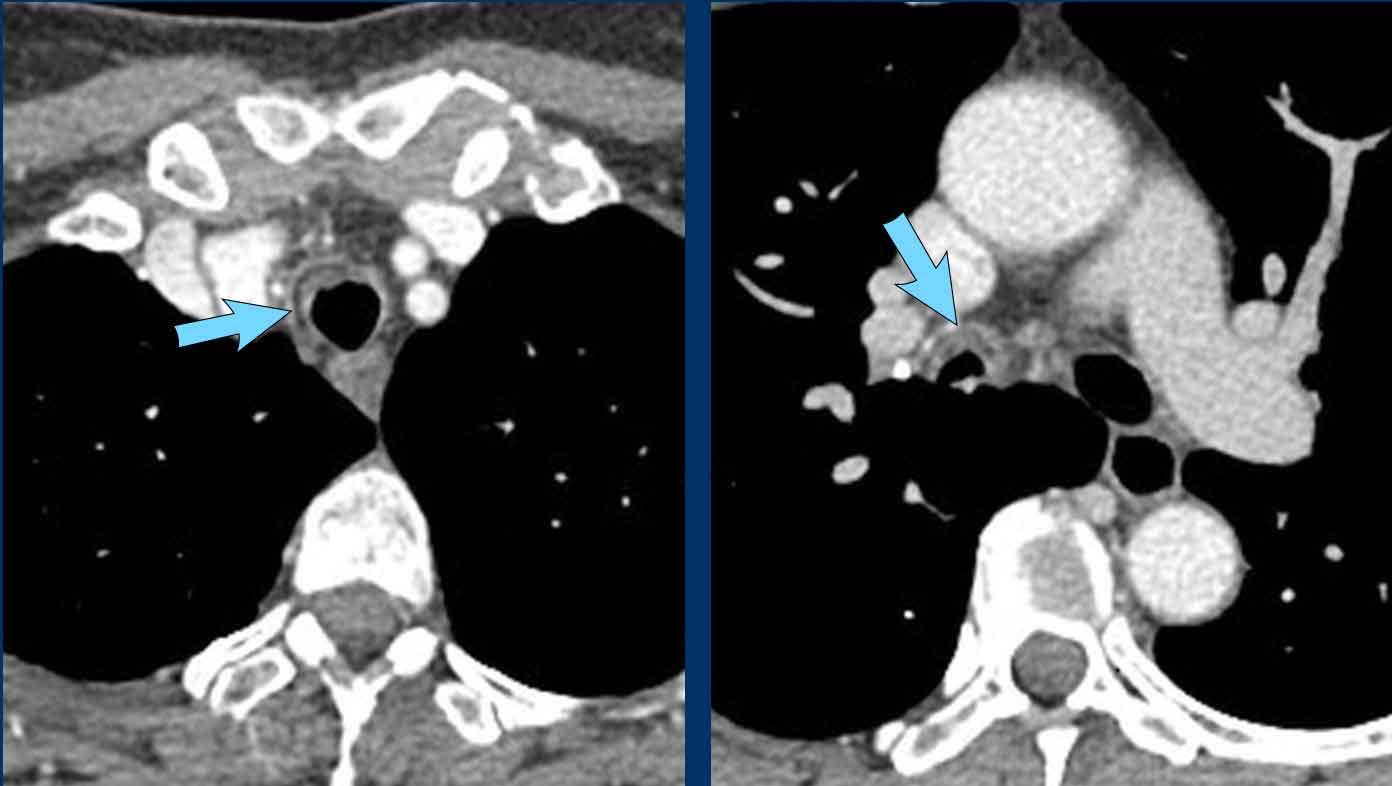

Chèn ép phế quản chính phải do hạch bạch huyết to.

Bệnh nhân này có cung động mạch chủ đôi gây chèn ép khí quản.

Hình ảnh

Viêm trung thất xơ hóa bên phải ở nam giới 51 tuổi, cho thấy tổn thương tỷ trọng mô mềm xung quanh phế quản chính phải (mũi tên).

Cùng bệnh nhân.

Có các dấu hiệu thứ phát của chèn ép đường thở trung tâm và mạch máu, với mất thể tích phổi khu trú và dày mô kẽ do phù nề.